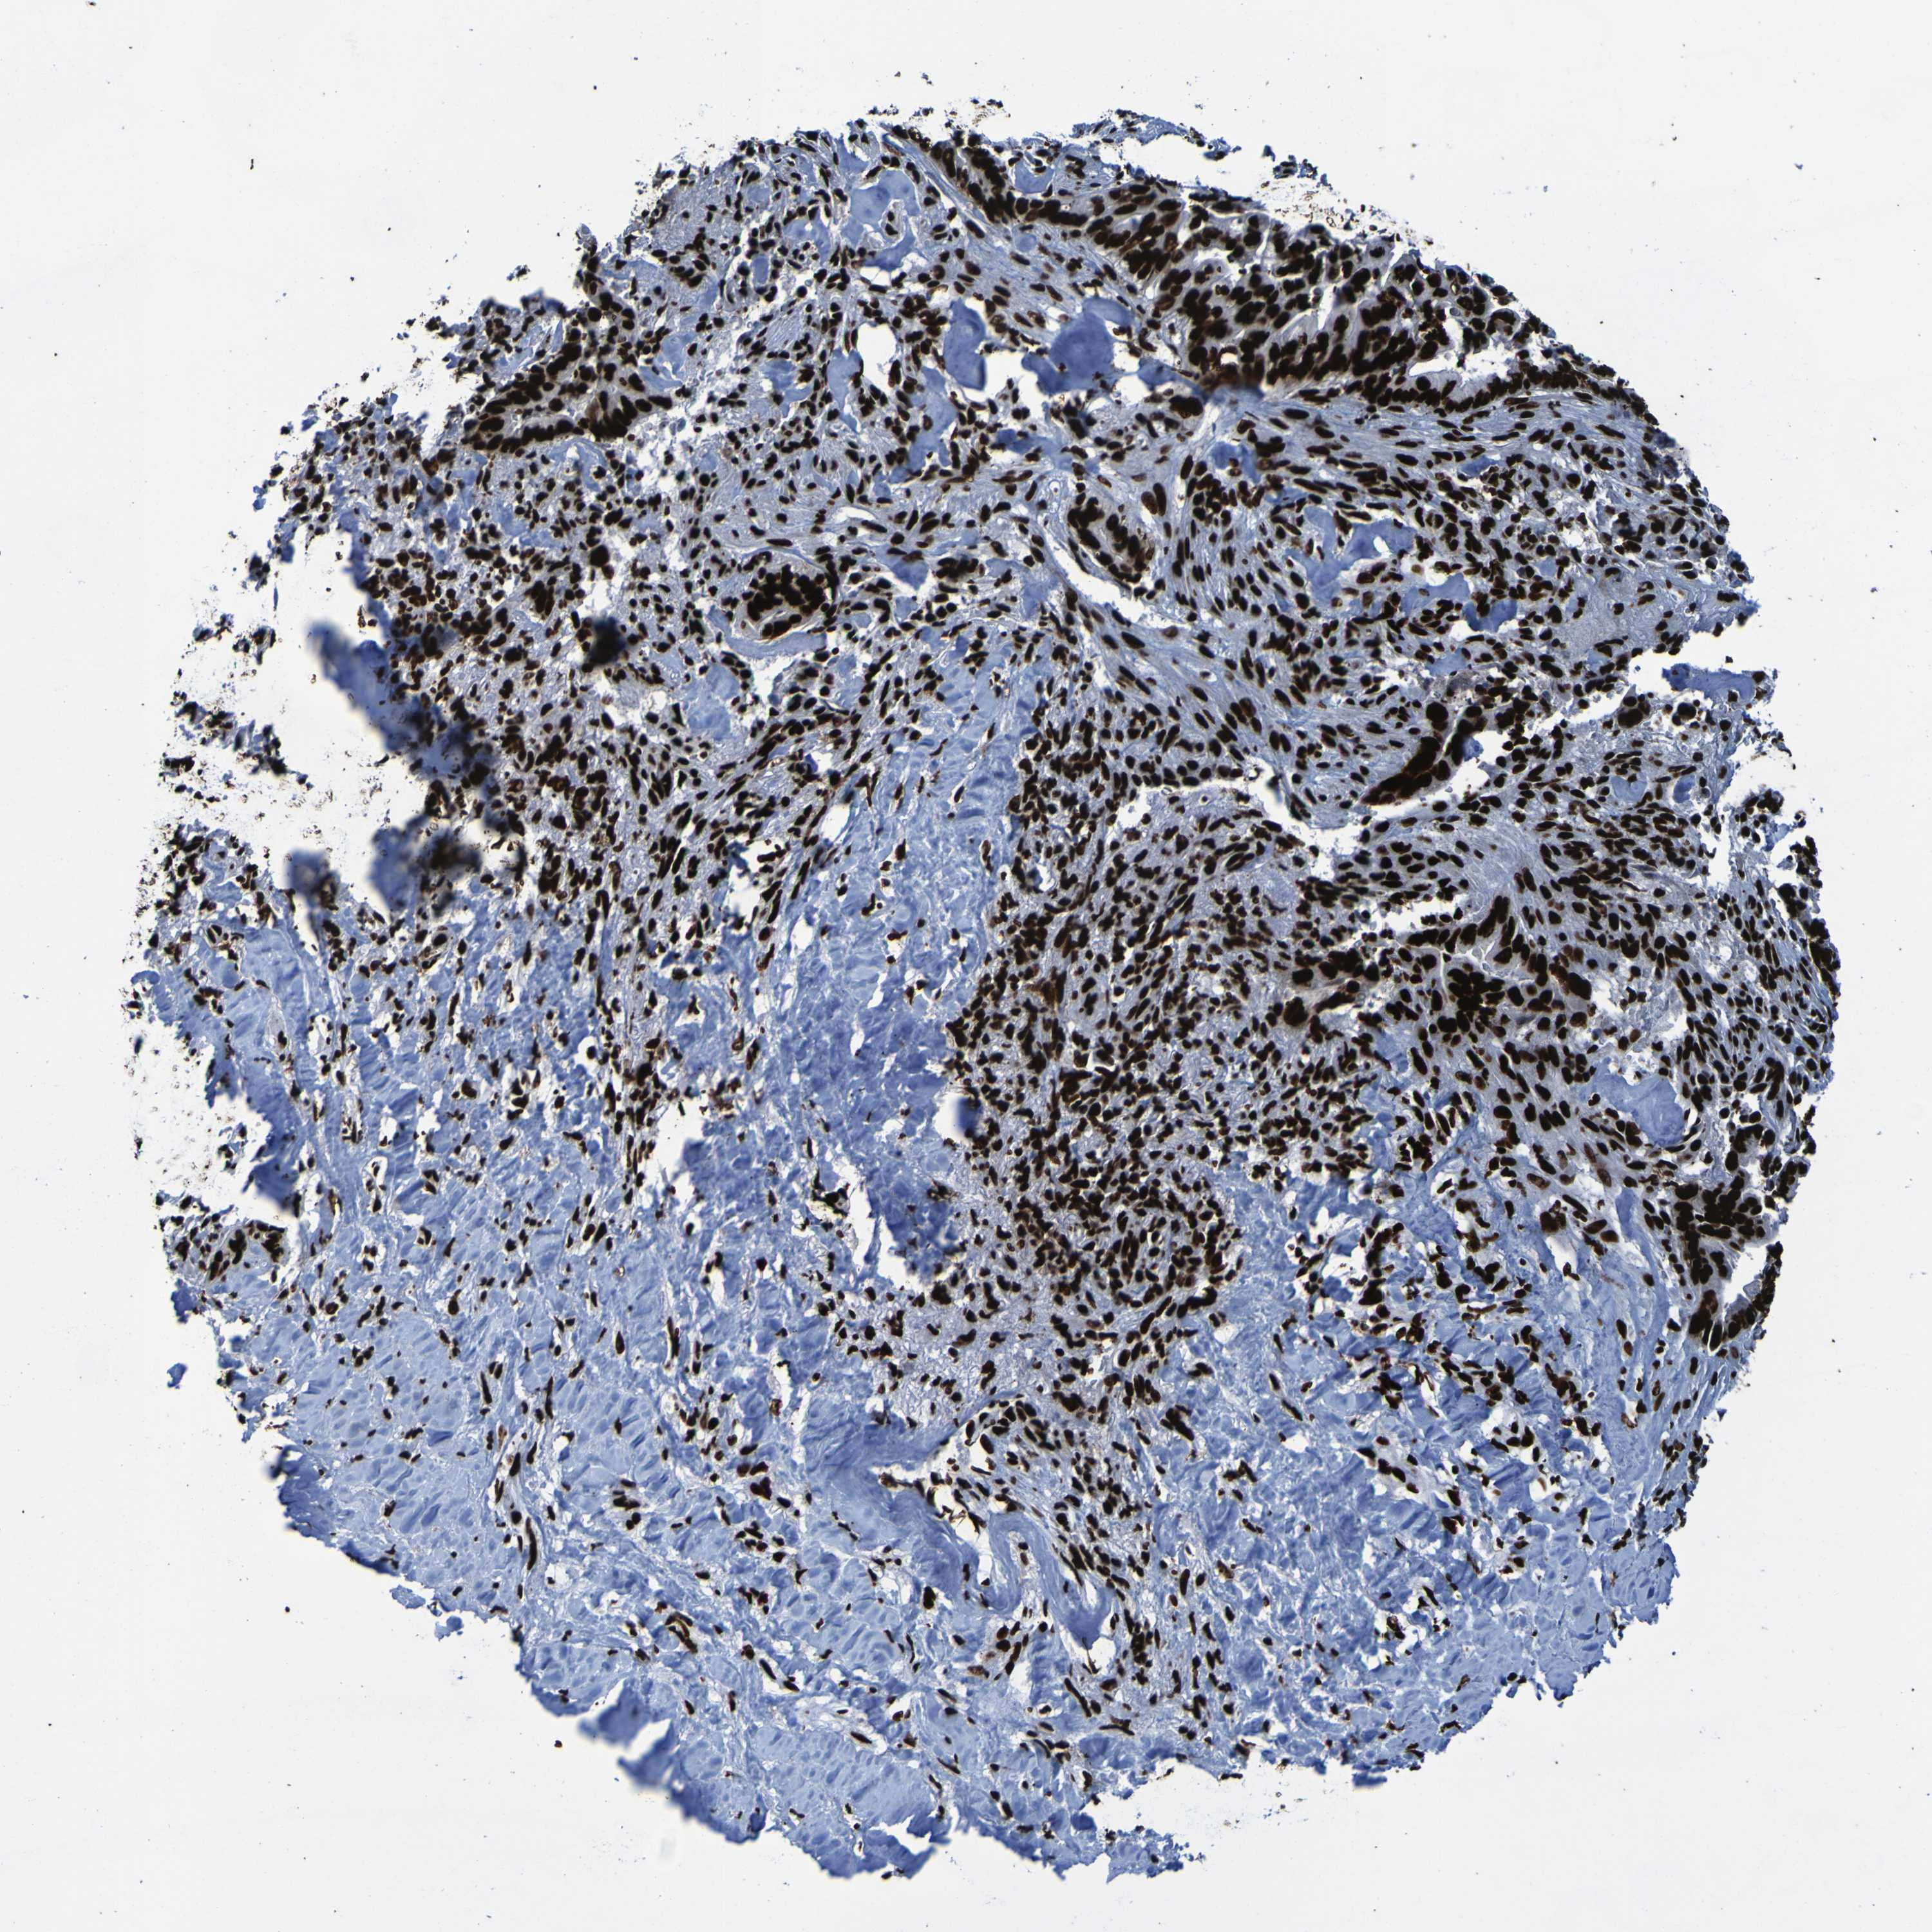

LIVER CANCER - Protein expressioni

A mouse-over function shows sample information and annotation data. Click on an image to view it in a full screen mode. Samples can be filtered based on level of antibody staining by selecting one or several of the following categories: high, medium, low and not detected. The assay and annotation is described here.

Antibody stainingi

Antibody staining in the annotated cell types in the current human tissue is reported as not detected, low, medium, or high, based on conventional immunohistochemistry profiling in selected tissues. This score is based on the combination of the staining intensity and fraction of stained cells.

Each image is clickable and will lead to virtual microscopy that enables deeper exploration of all samples and also displays staining intensity scores, fraction scores and subcellular localization as well as patient and tissue information for each sample.

Antibody CAB012983

Staining

Medium

Moderate

75%-25%

Cytoplasmic/membranous

Cytoplasmic/membranous,nuclear

Cholangiocarcinoma